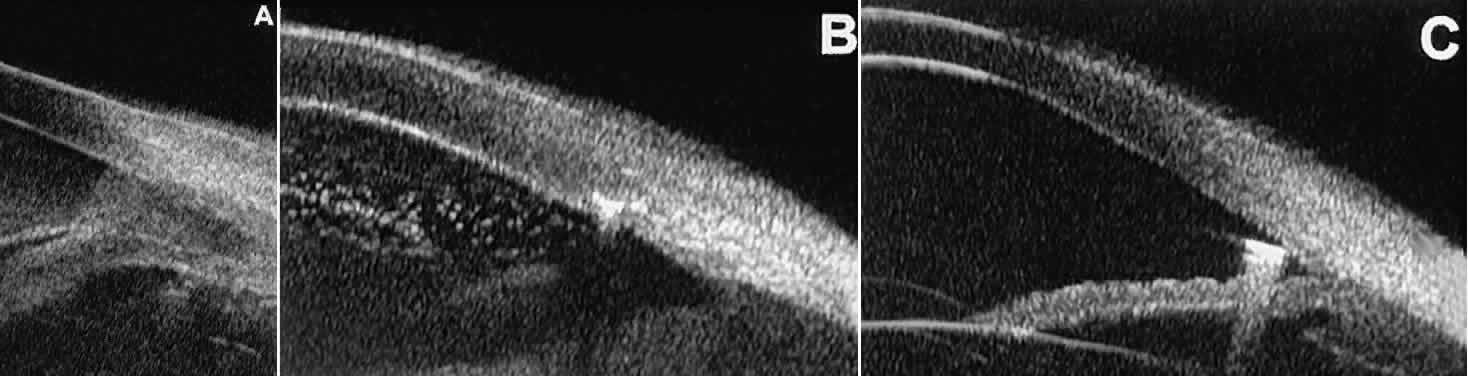

Postoperative UBM imaging of the anatomic changes caused by glaucoma surgery often helps to explain mechanisms of success and failure of the various surgical procedures (Fig. 12).3,4 After laser iridotomy, UBM can show whether the iridotomy is partial thickness (see Fig. 12A) or full thickness (see Fig. 12B) and whether the plane of curvature of the peripheral iris has changed compared with the pretreatment findings. After trabeculectomy (see Fig. 12C), UBM can show whether the scleral aperture is patent or blocked internally, whether the peripheral iridectomy is open or blocked, and whether the filtering bleb is flat, shallow, or deep.9 After tube shunt surgery (see Fig. 12D), UBM can show the position of the tip of the tube and whether its orifice is open or plugged.

Fig. 12. UBM features in glaucomatous eyes after treatment or filtering surgery. A. Incomplete peripheral iridectomy created by laser. B. Full-thickness peripheral iridectomy created by laser. C. Postoperative features of trabeculectomy including peripheral iridectomy, inner scleral defect, thin residual scleral flap, and overlying conjunctival filtering bleb. D. Tube shunt projecting radially into anterior chamber; note that the tube “shadows” deeper structures.